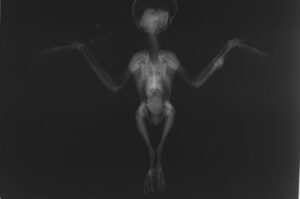

整復オペ Before & After

レントゲン検査の結果、左翼の「尺骨」という骨に、骨折が認められました。体重がわずか180gしかない非常に小さな体のため、あまり重い固定器具を使うことはできません。今回は脊髄麻酔用の特殊な注射針を、骨を固定するピンに改造して利用しました。

ピンを入れた骨が完全に付くまで、翼はテーピングでしっかりと固定します。しばらくは狭いケージの中で我慢の日々を過ごしてもらいました。オペを行ってから18日後、レントゲン検査の結果、骨折していた骨が癒合していることが確認されました。もう固定具は必要ありません。ピンを抜き、飛翔訓練の始まりです。